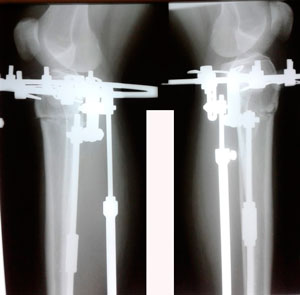

в процессе работы